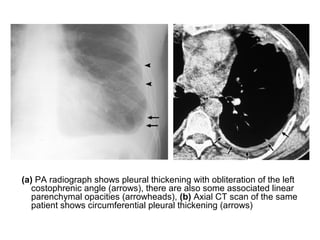

(a) PA radiograph shows pleural thickening with obliteration of the left

costophrenic angle (arrows), there are also some associated linear

parenchymal opacities (arrowheads), (b) Axial CT scan of the same

patient shows circumferential pleural thickening (arrows)